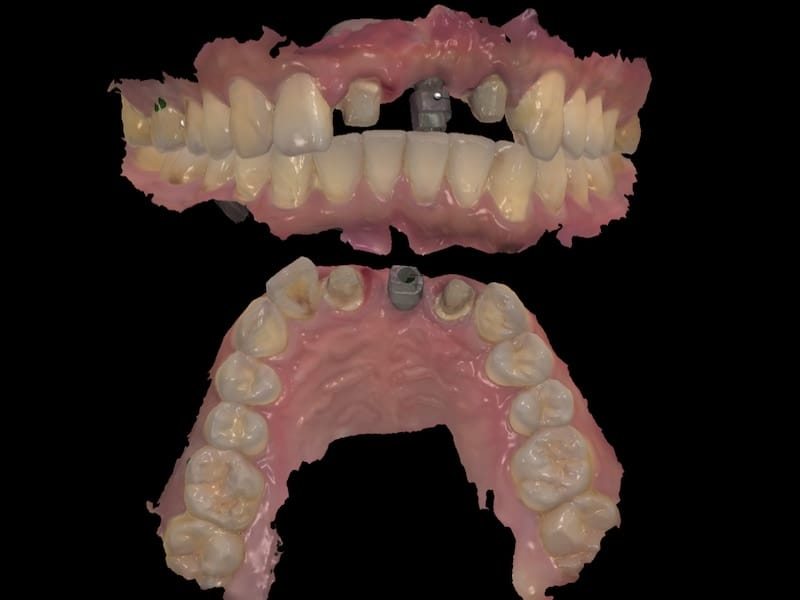

植入後等待大約四個月左右,植牙牙根和齒槽骨的骨整合完成,我們就可以開始製作假牙。牙科數位科技的進步,能夠讓我們利用電腦數位口內掃描的方式執行假牙製作流程。並且有很專業的牙技師配合,除了精準、效率,我們也能讓成品更加擬真。

利用數位口腔掃描,快速獲得口內上下顎 3D 模型 數位口掃 3D 模型,連咬合狀態也能清楚呈現